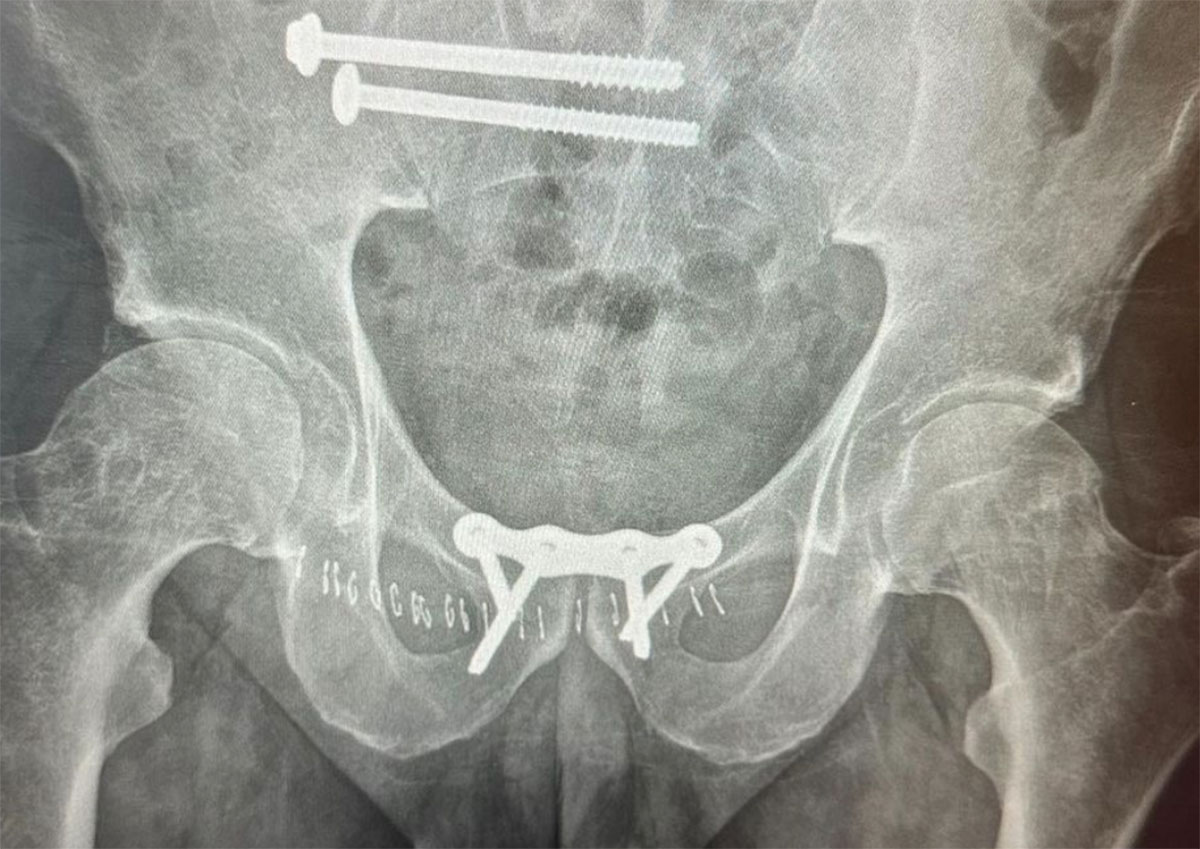

Amazingly, they were able to cross the border and get Coco to a hospital stateside. Within a few hours, he was in surgery and the nightmare was finally coming to an end. Now, he’s got a metal plate under his bladder that’s holding his pelvis together and two enormous screws in his sacrum. From the time he had his first x-ray in Mexico to the time he got his surgery, the fracture in his pelvis had widened from 13 millimeters to 36 millimeters.